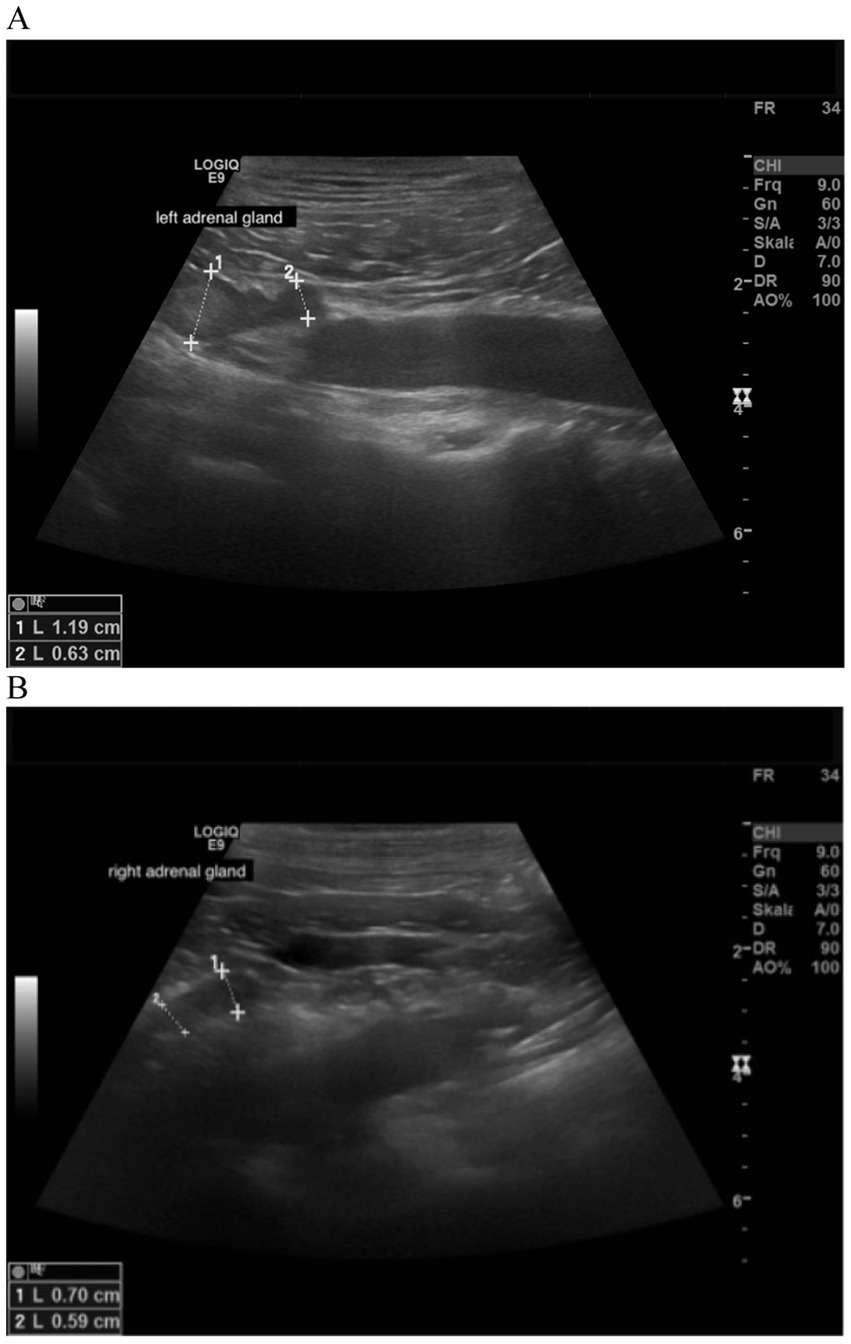

Figure 5

www.frontiersin.org

Figure 5. Ultrasound image of the left and right adrenal gland in a dog with adrenal asymmetry and a suspected myelolipoma. (A) In the cranial pole of the left adrenal gland, a round hyperechogenic lesion was present. Measurements were 1.19 cm at the cranial pole and 0.63 at the caudal pole. Revaluation of the adrenals was performed after 18 months. At this time, the cranial and caudal pole of the left adrenal gland measured 1.19 and 0.75 cm. (B) cranial and caudal pole of the right adrenal gland measuring 0.59 and 0.7 cm.

In 38 dogs, images of adrenal glands were archived and were available for evaluation of adrenal shape and echogenicity. Thirty-two (84.2%) had a physiological longitudinal oval shape. In 6 dogs (15.8%), nodular hyperplasia of one adrenal gland was present, whereas the contralateral adrenal gland had a physiological shape (Table 8). In two of these dogs a central lightening was present, which was addressed as adrenal myelolipoma (5.3%). Figure 5 shows the adrenal glands of a dog with suspected myelolipoma.

Regarding the echogenicity, the adrenal glands were both physiologically hypoechogenic in 32 dogs (84.2%), whereas in 5 dogs (13.2%) one of the two adrenals was hyperechogenic. In 1 dog (2.6%), one of the two adrenal glands had an inhomogeneous parenchyma. (Table 9). In none of the 38 dogs were thrombi formation or tumor invasion of vascular venous system identified.